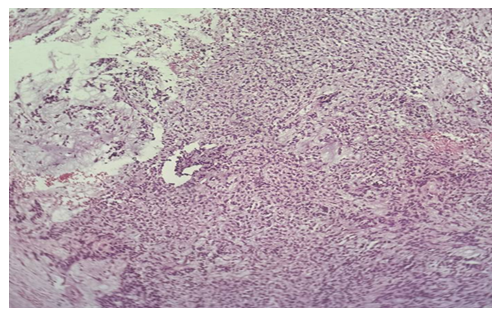

| Picture 2. Surgically resected specimen of salivary gland tumor. Histological appearance of pleomorphic adenoma (mixed tumor), localized in the left parotid gland (1 case; No. 2755). The tumor demonstrates biphasic morphology with epithelial and myoepithelial components embedded in a heterogeneous myxoid–chondroid stroma (H&E stain) |

Morphological description: The section reveals a well-circumscribed salivary gland neoplasm composed of uniform epithelial cells with round to oval nuclei and scant cytoplasm. The tumor grows in a solid and trabecular pattern with minimal cellular pleomorphism. Adipose tissue infiltration is seen at the periphery, but the neoplasm maintains a distinct border from surrounding structures. No chondromyxoid stroma or mixed tissue elements are identified, which distinguishes this tumor from pleomorphic adenoma. Figure 3. Histological section of monomorphic adenoma of the submandibular gland showing uniform epithelial cells arranged in solid and trabecular patterns with sharp demarcation from adjacent adipose tissue. No stromal heterogeneity is observed (H&E stain, ×20). | Figure 4a. Pleomorphic adenoma |

Morphological description: Histological examination reveals a well-circumscribed tumor with a characteristic mixed architecture. Epithelial and myoepithelial cells form irregular duct-like and trabecular structures. The stroma is markedly heterogeneous, demonstrating areas of myxoid, chondroid, and fibrous components. This biphasic pattern with variable stromal composition is a hallmark of pleomorphic adenoma. No signs of malignant transformation are seen in the examined section. Figure 4a. Pleomorphic adenoma of the parotid gland showing mixed epithelial and myoepithelial cell proliferation with heterogeneous stromal components, including myxoid and chondroid areas (H&E stain, х10).  | Figure 4b. Pleomorphic adenoma |

Morphological description: Microscopic examination demonstrates epithelial and myoepithelial cell proliferation forming duct-like and solid structures embedded within a myxochondroid stroma. The stroma exhibits cartilaginous differentiation with lacunae containing chondrocyte-like cells, a typical feature of pleomorphic adenoma. Foci of hemorrhage and vascular congestion are also observed. The biphasic pattern of epithelial and stromal elements further supports the diagnosis of pleomorphic adenoma. Figure 4b. Pleomorphic adenoma of the parotid gland showing epithelial and myoepithelial proliferation embedded in myxochondroid stroma with chondrocyte-like cells. Biphasic morphology is characteristic of pleomorphic adenoma (H&E stain, х20). | Figure 4c. Pleomorphic adenoma |

Morphological description: The histological field demonstrates a classic pleomorphic adenoma structure with epithelial nests and cords immersed within a chondromyxoid stroma. The stroma shows cartilaginous differentiation with chondrocyte-like cells in lacunae, while epithelial components form duct-like structures. The transition between epithelial and stromal elements is gradual, underlining the mixed (biphasic) nature of the neoplasm. This morphology is diagnostic for pleomorphic adenoma. Figure 4c. Pleomorphic adenoma of the parotid gland showing epithelial cords within a chondromyxoid stroma, with areas of cartilaginous differentiation and chondrocyte-like cells (H&E stain, х20). | Figure 4d. Pleomorphic adenoma |

Morphological description: The section demonstrates a biphasic tumor composed of epithelial cell islands intermixed with a myxoid and fibrous stroma. Epithelial elements form trabecular and duct-like structures, while the stroma displays loose myxoid areas with scattered spindle-shaped myoepithelial cells. Focal areas of hyalinization are also present. These features are characteristic of pleomorphic adenoma, confirming its mixed histological architecture. Figure 4d. Pleomorphic adenoma of the parotid gland composed of epithelial cell nests within a myxoid and fibrous stroma. Trabecular structures and hyalinized areas are observed, consistent with pleomorphic adenoma morphology (H&E stain, х20). | Figure 5a. Adenocarcinoma, stage I |